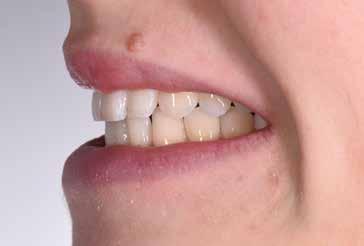

97 96 ESTETICA FUNZIONE POSTURA 145 _ Profilo sinistro con sorriso. 146 _ Ripresa di 3/4 sinistra con sorriso. 147 _ Immagine frontale naturale, senza sorriso. 148 _ Immagine frontale con sorriso. 149 _ Ripresa di 3/4 destra con sorriso. 150 _ Profilo destro (senza) con sorriso. 151 _ Dettaglio del sorriso. 152 _ Dettaglio del sorriso nel profilo destro. 153 _ Dettaglio del sorriso nel profilo sinistro.

Fig. 20 > Sorriso laterale destro.

Fig. 21 > Sorriso laterale sinistro.